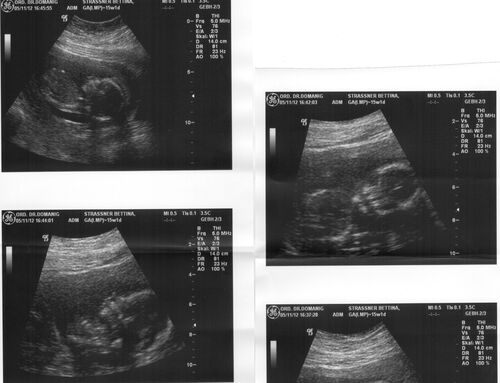

Jaaaaaaa.........Nach langem Warten und Hoffen freuen sich meine Eltern Harald und Bettina schon sehr auch meinen errechneten Geburtstermin am 24.04.2013. Ich werde ein Stier ganz wie mein Opa Karl gewesen ist..... Zufälle gibts im Leben also wirklich unglaublich.